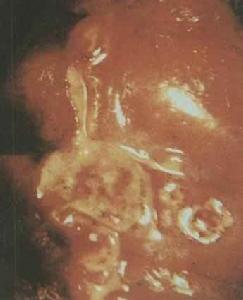

一般潰瘍面常有少量出血,是因潰瘍底部毛細血管遭受腐蝕、破壞所致,當潰瘍底部較大的血管,不論是動脈或靜脈被腐蝕破裂均可引起大出血。潰瘍進展過程中,底部組織不斷被侵蝕,潰瘍不斷加深,最後可穿透胃或十二指腸壁的漿膜層而引起穿孔,急性穿孔常見於前壁潰瘍,由於十二指腸或胃內容物流入腹腔,導致急性瀰漫性腹膜炎;慢性潰瘍穿透常見於後壁潰瘍。幽門前區、幽門管或十二指腸潰瘍在癒合過程中可形成大量瘢痕,由於瘢痕組織收縮可引起幽門器質性狹窄,也可因潰瘍周圍繼發炎症、水腫或幽門肌痙攣而導致功能性幽門梗阻。

無論是胃潰瘍或十二指腸潰瘍均可並發出血,尤其是大潰瘍及深潰瘍常易腐蝕潰瘍基底部的血管而發生出血,幽門管潰瘍及十二指腸壺腹後潰瘍更易導致出血且出血後常不易止血。